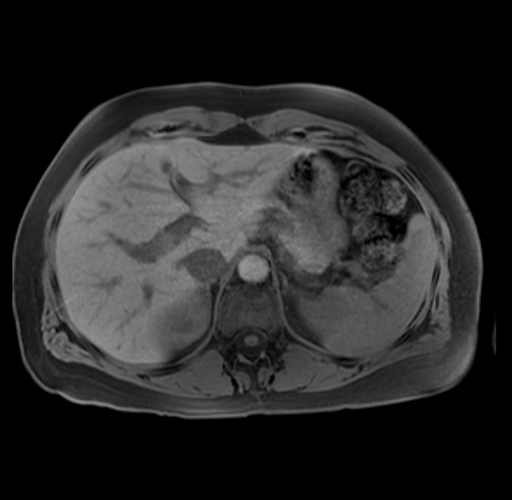

Imaging Analysis

Look through the patient's CT scan to identify any areas of concern for the necessary procedure.

Based on your CT findings, which issue(s) are present and would give reason for "planned slowing down moment(s)" in this case?